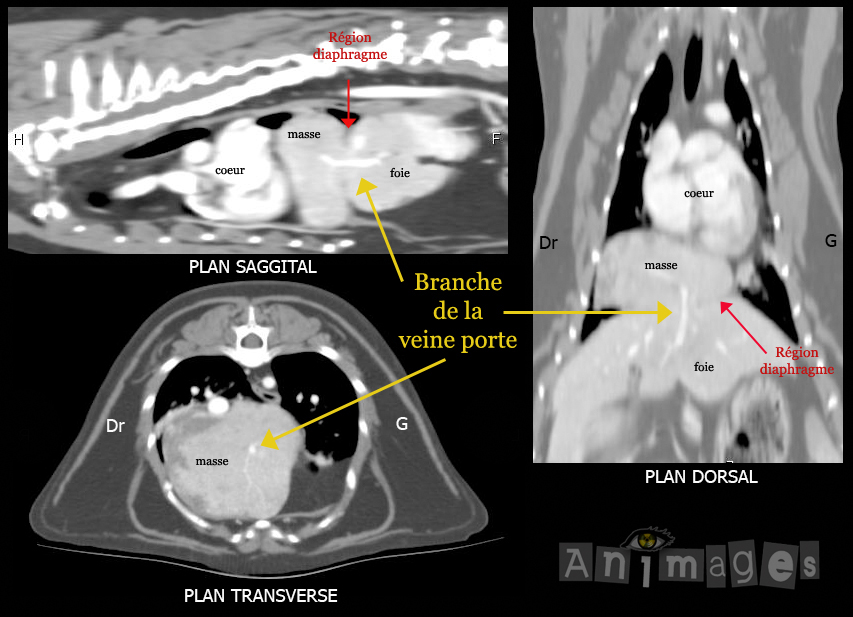

Tomodensitométrie